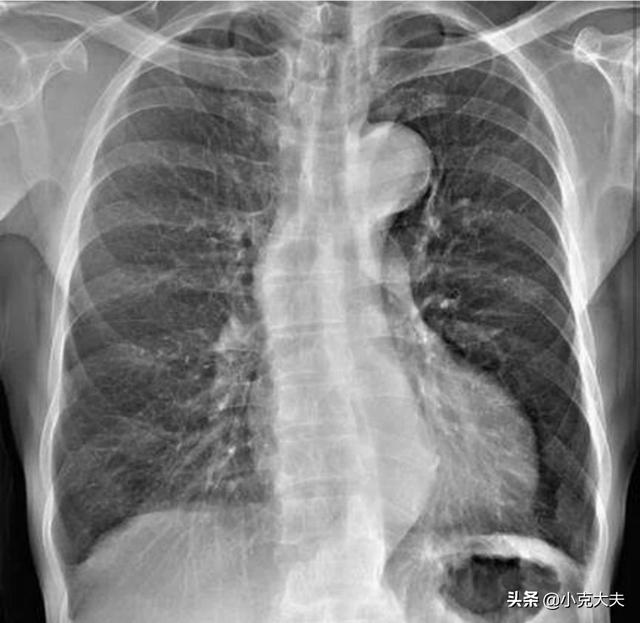

1、爪のベッドチアノーゼは、主に肺病変、肺機能障害、換気と過換気の異常のために、肺の病変が完全に外套気管支炎、肺気腫、肺水腫などのような、によって引き起こされる酸素を使用することはできません重度の肺病変を持つ患者に見られる。

2、爪床チアノーゼに加えて、慢性肺疾患の一部の患者はまた、主に肺疾患のため、指の端に慢性低酸素症、中毒などによって引き起こされる、ドラムスティック指としても知られている杵指を表示することができ、血流は、毛細血管の拡大と過形成、肥大、拡幅の出現に起因する軟部組織で比較的豊富であり、指の端から爪の根元の症状は、肺膿瘍、気管支拡張、肺がんの一部に見ることができるアーチ状の膨らみの端に、。原因不明の杵指が最初の症状である患者。また、指の関節に原因不明の痛みを伴う患者もいる。